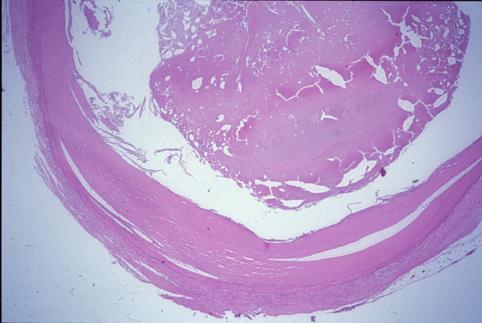

Criteria of Hist.ClassificationTumor-like lesions/Calicified wall lesion

LocationLarge intestine(Colon)/Descending colon

Size10 - 14